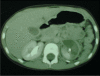

Renal trauma associated with blunt abdominal trauma is common. Children presenting with grade 4 or 5 renal lacerations who are hemodynamically stable can be followed safely nonoperatively. No long-term complications from conservative management have been noted.